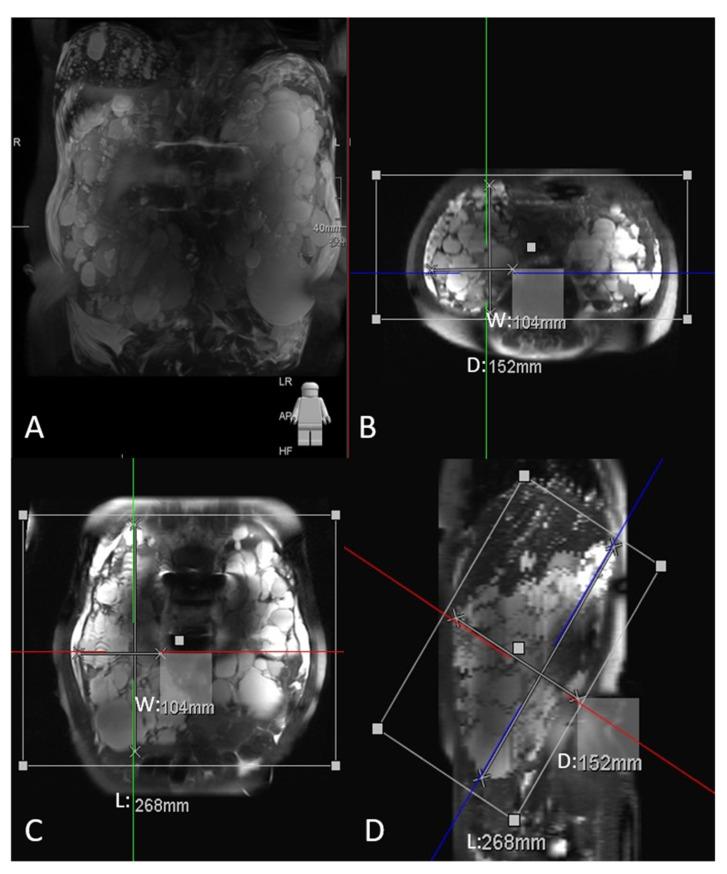

多囊肾病患者腹部肌肉量的定量及肌肉减少症的横断面成像诊断:与总肾体积的相关性

Quantification of Abdominal Muscle Mass and Diagnosis of Sarcopenia with Cross-Sectional Imaging in Patients with Polycystic Kidney Disease: Correlation with Total Kidney Volume.

Background: Polycystic kidney disease (PKD) is an inherited disorder characterized by renal cysts that may mask lean body loss. This study quantified and compared muscle mass by using computed tomography (CT) and magnetic resonance imaging (MRI) images between the PKD and control groups and correlated muscle mass with total kidney volume (TKV). Methods: We retrospectively enrolled patients who had a new diagnosis of PKD from May 2015 to May 2016. The CT and MRI images at the third lumbar level were processed to measure the total abdominal muscle (TAM) area for the diagnosis of sarcopenia, and TKV was estimated using the ellipsoid formula. Results: We included 37 women and 25 men (mean age: 50.40 years) in the PKD group. There was no difference in body mass index and albumin levels, but significant differences in creatinine level (p < 0.001), TAM area (p = 0.047), and TKV (p < 0.001), were noted between the two groups. A significantly negative correlation was observed between TKV and TAM area after adjustment for body height (r = −0.217, p = 0.003). Conclusions: CT and MRI images can accurately diagnose sarcopenia, which may be masked by cysts in patients with PKD.

摘要